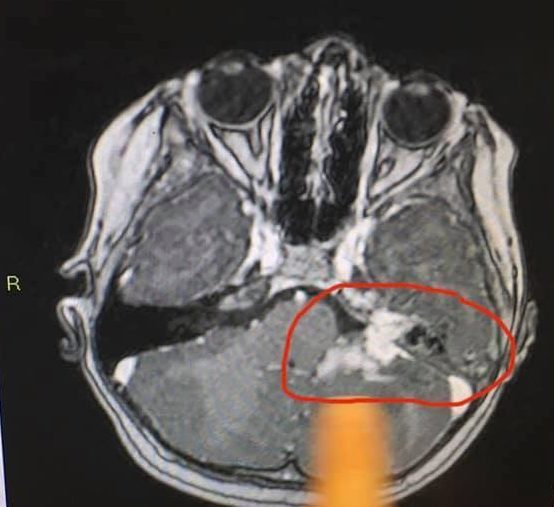

The infection then spread to her brain. She was taken to Wishaw where Ameilia was diagnosed with three abscesses in her brain after the CT scan results.

Jemma said: “Caused by a bacterial infection which probably entered her brain through the ear. She needed immediate treatment, but Wishaw was not equipped for this kind of condition.”

She was transferred to the Royal Hospital for Sick Children in Glasgow where the parents were told that it was a life-threatening infection and Ameilia needed to start IV antibiotics straight away.